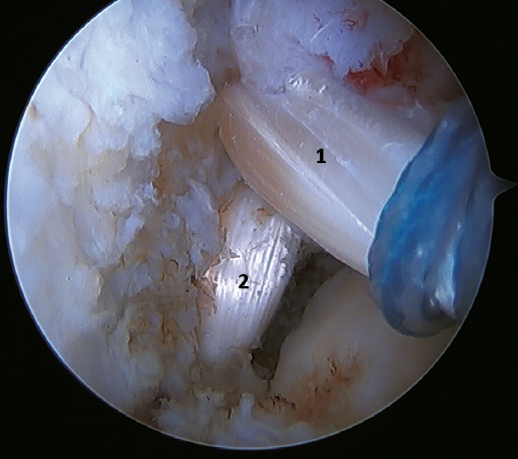

Another point of interest is the presence of os subfibulare. In these cases, we have the option of fixation, although this is usually not feasible and the best therapeutic option is excision and reconstruction, due to the impossibility of direct repair(60)(Figure 4).